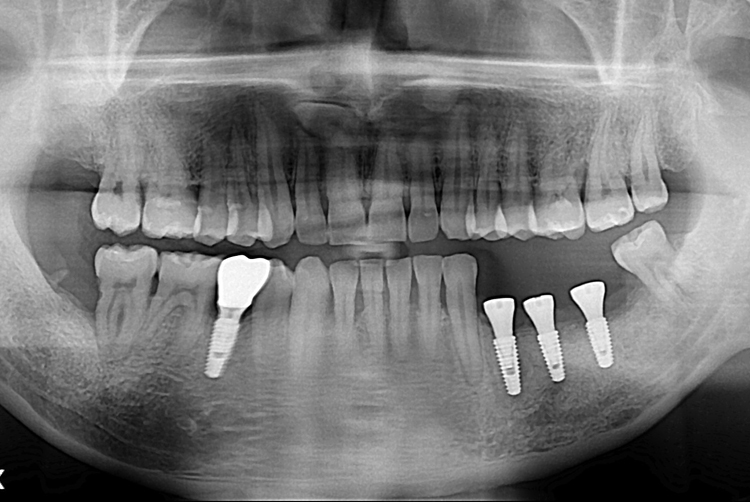

[임플란트] 어금니 임플란트

치료후 : 2019-11-29

세종치과는 많은 환자와 다양한 케이스를 바탕으로

항상 편안한 임플란트 수술을 제공하고자 노력하고,

오래동안 튼튼히 쓸 수 있는 임플란트 수술을 가장 큰 목표로 삼고 있습니다.